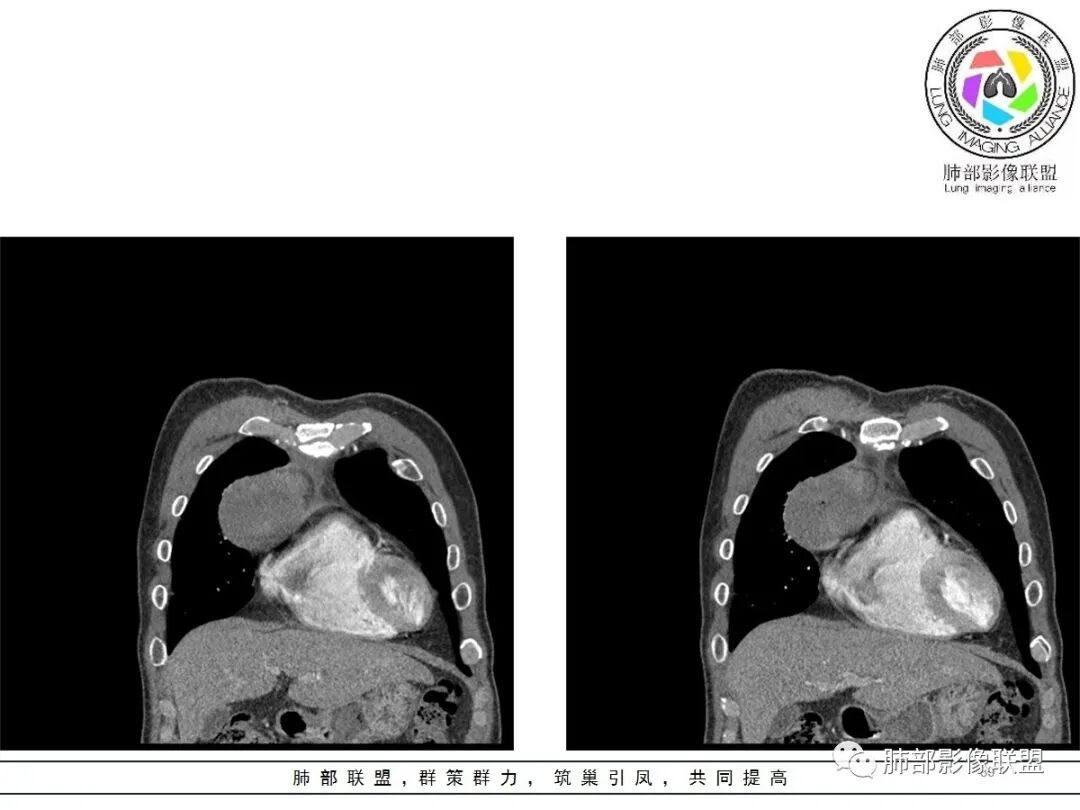

周围脂肪间隙密度增高,内部小点状很低密度影

右侧少量胸水

19日,4天后, 内部低密度影有,周围渗出增多,胸水增多

薄膜状强化

影像上周围病灶变化明显

常规肿瘤侵犯不支持,太快

应该是炎性病变渗出

脂肪密度明显,还有钙化、囊性病变,支持含脂质类病变破裂

周围是化学性炎症或出血所致

后期强化,可能与炎症有关

可能:1、肿瘤或瘤样病变破裂出血或内部物质外溢所致2、炎性病变所致

对比一下:

肿瘤样病变破裂所致纵隔炎应该没错

南边:肿瘤或肿瘤样病变破裂所致纵隔炎,这是大方向

2.胸膜掀起,右侧内乳动脉略增粗,定位右前上纵隔内占位。

3.右上纵隔囊实性占位,边界清楚。中央见点状脂肪密度影,边缘见一点状钙化影,增强不均匀环形强化。

4.四天内病灶变化快,块影增大且不规则,包膜似不完整,边界不清,上份可见浸润或渗出,与周围心脏大血管及心包等间隙不清。胸水增多。

5.未见明显淋巴结增大

第一次的检查符合胸腺瘤影像学改变,短期内的形态学改变及突然出现的边界模糊或浸润等,符合出血或炎症。